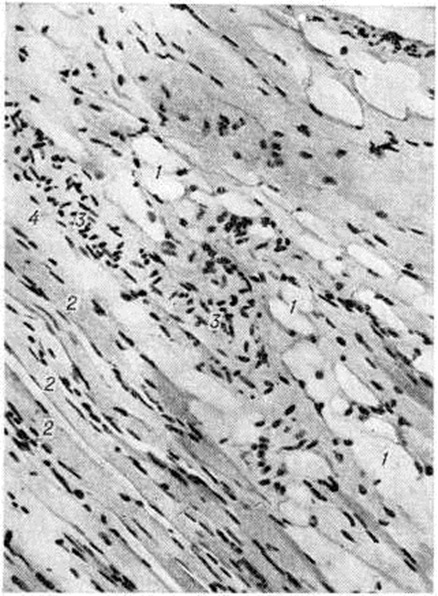

Поражение кожи при системной Склеродермия часто сочетается с поражением суставов, костей и мышц. При поражении суставов обнаруживается экссудативно-пролиферативный синовит (смотри полный свод знаний) с фибринозными наложениями на поверхности синовиального слоя суставной капсулы, очаговой пролиферацией синовиоцитов, единичными продуктивными васкулитами, умеренно выраженным ангиоматозом, лимфоидно-макрофагальной инфильтрацией в субсиновиальном и фиброзном слоях. Суставной хрящ при системной Склеродермия теряет эластичность, становится ломким и быстро изнашивается; отмечается околосуставной остеопороз (смотри полный свод знаний). При отсутствии признаков артрита в суставной полости фактически отсутствует синовиальная жидкость, макроскопически синовиальный слой суставной капсулы становится плотным, лишённым ворсинок. При гистологический исследовании с трудом удаётся найти её органоспецифические особенности: синовиоциты на большем протяжении отсутствуют, синовиальный слой покрыт гиалиноподобными массами, субсиновиальный слой представлен бедной сосудами фиброзной соединительной тканью с обширными полями гиалиноза. При системной Склеродермия, сопровождающейся миопатическим синдромом, гистологический исследование скелетных мышц выявляет картину хронический миозита (смотри полный свод знаний) с разнокалиберностью мышечных волокон, гидропической дистрофией и миолизом части их, периваскулярными инфильтратами из лимфоцитов, макрофагов, полинуклеаров, васкулитами, разрастанием грануляционной и фиброзной соединительной ткани в эн дои перимизии. Более характерен фиброзирующий интерстициальный миозит (рисунок 3) с выраженным склерозом, липоматозом, гиалинозом эпи и перимизия, склерозом стенок сосудов, запустеванием капиллярного русла, мелкоочаговой периваскулярной лимфоидно-макрофагальной инфильтрацией, единичными васкулитами, очаговой перифасцикулярной или диффузной атрофией мышечных волокон.